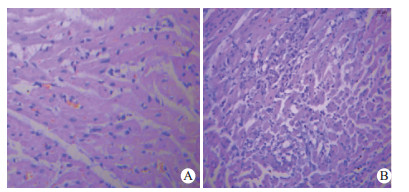

HE染色后光镜下观察显示,UTI组心肌纤维排列尚整齐,肌纤维肿胀,可见少量断裂,细胞核形态,大小不均匀,心肌间质可见少量炎症细胞浸润(图 3A)。对照组心肌纤维肿胀断裂、扭曲,呈波浪状,排列极度紊乱,伴有横纹消失,并可见大片心肌纤维溶解坏死,心肌间质可见大量炎症细胞浸润,间隙增宽,心肌细胞出现空泡变性及溶解,心肌细胞形态欠规则,大小不均(图 3B)。

| A: UTI组心肌组织病理学改变;B:对照组心肌组织病理学改变 图 3 UTI组和对照组心肌组织病理学改变(HE×200) Fig 3 Myocardiac histopathological changes in the UTI and control groups (HE×200) |

光镜下,ROSC后通过HE染色后可见心肌组织出现明显缺血改变。室颤后脑组织内出现持续的缺血缺氧,在约4 min后脑内储存的能量即消耗殆尽,此时细胞外Na+内流,触发Na+- Ca2+交换体,增加Ca2+内流,细胞内钙超载又激活蛋白酶,直接破坏生物膜的完整性,进一步扩大炎症、氧化应激反应[14]。UTI组药物干预后较对照组心肌组织病理损伤有明显减轻,UTI可明显稳定细胞膜, 减少ROSC后早期能量消耗、减轻钙超载、减少氧自由基释放等级联效应有关。